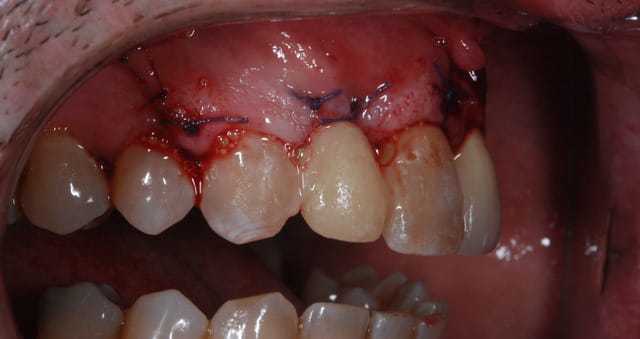

pas que pour le granulome...d'ailleurs...mais aussi parce que tu as une belle fracture vestibulaire qui fait que la corticale...bein y en a plus...ou quasi plus...

dans un cas comme çà, pour moi c'est extraction, curetage méticuleux, éponge hémostatique, une petite suture en haut pour bien tout stabiliser sans trop de tension et un petit bridge prov collé fait au composite, pourquoi pas "armé" avec une tresse résine (que tu trouves en petites bobines chez les vendeurs de maquettes...)

2 à 3 mois plus tard, tu peux ré-intervenir pour faire ton aménagement osseux, selon les résultats du scan, de l'expansion avec pose de l'implant jusqu'à la greffe avec un bloc en passant par la ROG (avec ou sans box technique)...bref, tout dépend de la cicat...;-)

beau travail, mais

les 2 cas ne me semblent pas comparable dans la mesure ou tu as réussi à préserver un bandeau d'os vestibulaire presque au niveau des collets. Il permet un effet piquet de tente incomparable et évite les mauvaises surprises de perte importante de volume de biomat a la cicatrisation.

Dans l'autre cas la table vestibulaire est manquante, le résultat d'une EII beaucoup moins prévisible et dans un secteur esthétique j'aime pas jouer a la roulette russe.